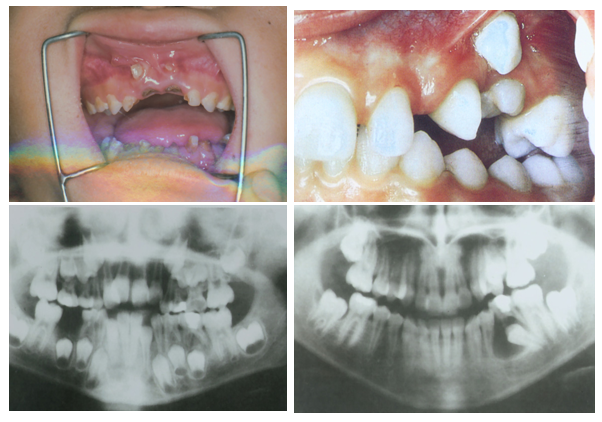

研究乳牙根管形态的方法有组织切片、镍钛锉探查、X线片、透明牙技术等,但均存在不足之处:组织切片样本量少,不够直观,来源困难;镍钛锉探查及X线平片具有不确定性,容易遗漏根管。

通过CBCT技术对乳牙根管系统进行研究,发现乳牙根管的基本规律如下:

• 乳前牙一般为单根管。

• 上颌乳磨牙大部分有3个牙根,远颊根和腭根常融合;近颊根可能有1~2个根管,远颊根和腭根都只有1个根管。

• 下颌乳磨牙的近中根常见2个根管,远中根常见1个根管,也有2个根管;近中根最常见Vertucci’s types Ⅳ类结构根管,远中根最常见Ⅰ类结构根管;少数存在5个根管。